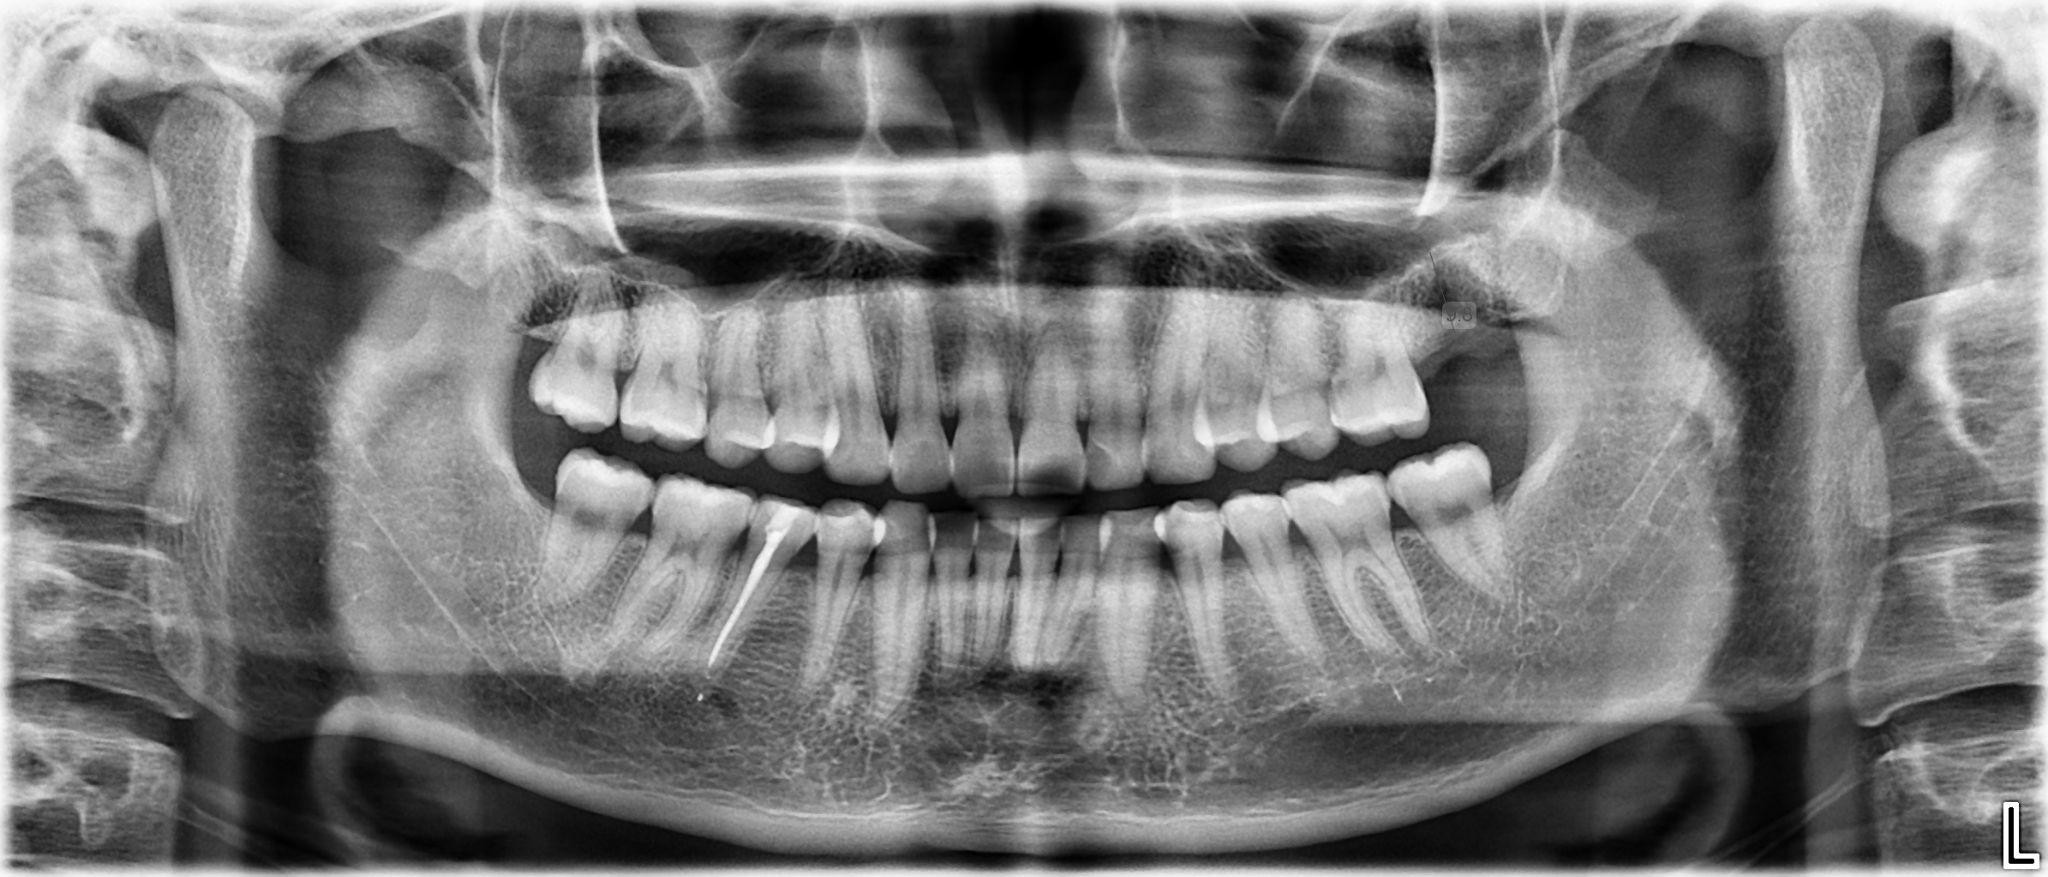

4. What option can be selected for upper jaw of this panoramic X ray?

5 / 23